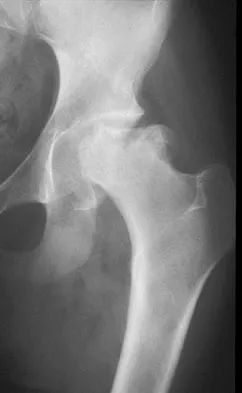

A 16-year-old high school football player sustains an injury to the left hip. The avulsed fragment identified by the arrow in Figure 34 represents the origin of which of the following structures?